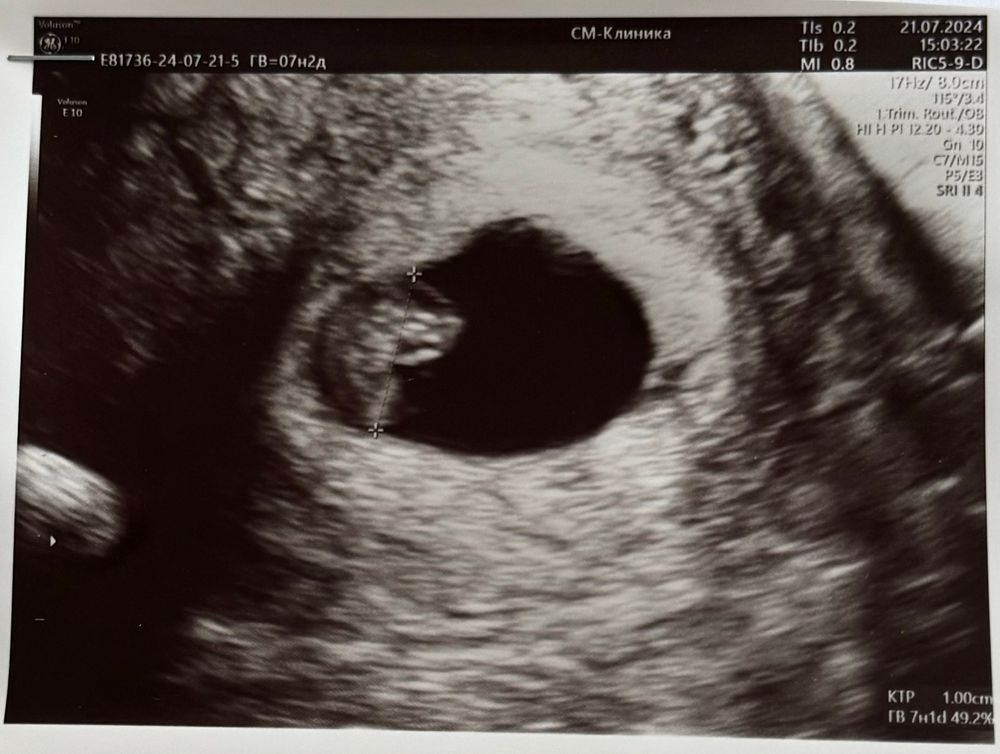

Результаты УЗИБыла на плановом УЗИ.

Увидела очертания настоящего человечка! Похожего, правда, на креветку)))

7н2д срок (32дпп).

КТР 10мм, ПЯ 20мм, ЖМ 4.8мм, ЧСС 141 уд/мин.